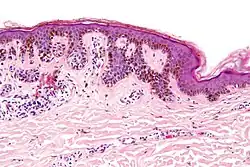

| Micrograph of a dysplastic nevus showing the characteristic rete ridge bridging, shouldering, and lamellar fibrosis. H&E stain. | |

Low magnification Low magnification

Intermediate magnification Intermediate magnification

Very high magnification Very high magnification